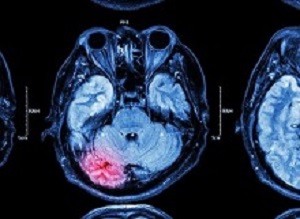

Traumatic brain injury (TBI) is among the most dreaded and tragic of diagnoses, notes a commentary in The Lancet. At least one clinical trial has shown that despite the most advanced care available, mortality from TBI, either in isolation or with concomitant polytrauma, can exceed 50%. Every physician who has cared for patients with TBI has felt the frustration that stems from being unable to alter the fatal course of traumatic brain haemorrhage in a previously healthy person.

Bleeding can potentially be targeted to alter the clinical course of TBI. Coagulopathy is a widely acknowledged contributor to TBI mortality and is associated with TBI severity. Although many aspects of coagulation function have been studied in this context, fibrinolysis is clearly a major driver of TBI-associated coagulopathy and haemorrhagic progression of injury. Clinical assessment of the antifibrinolytic drug tranexamic acid to reduce TBI-associated mortality is logical, particularly in view of the mortality reductions observed with tranexamic acid use in polytrauma patients without TBI and in women with post-partum haemorrhage.

The CRASH-3 trial collaborators report the results of a randomised, placebo-controlled trial of 12 737 adults with TBI (mean age 41·7 years [SD 19·0]; 80% men, 20% women). In patients treated within 3 h of injury, the risk of head injury-related death was 18·5% in the tranexamic acid group versus 19·8% in the placebo group (855 vs 892 events; risk ratio [RR] 0·94 [95% CI 0·86–1·02]). There was a significant reduction in risk of head injury-related mortality when tranexamic acid was administered within 3 h of injury to patients with mild-to-moderate TBI (RR 0·78 [95% CI 0·64–0·95]), but not in patients with severe head injury (0·99 [0·91–1·07]).

CRASH-3 is the first trial of a pharmacological intervention applied in the acute setting to show improved outcomes in patients with TBI. The use of 28-day head injury-related mortality as the primary endpoint probably biased the treatment effect towards the null because tranexamic acid is most likely to benefit patients with TBI with intracranial bleeding at risk of early mortality, whereas late deaths are unlikely to be affected by tranexamic acid. Indeed, the authors report that the greatest reduction in head injury-related deaths occurred in the first 24 h after injury in a manner consistent with that observed in CRASH-2. Future studies of tranexamic acid or other haemostatic interventions should reflect what is physiologically plausible and focus on endpoints of early bleeding-related death that clearly link intervention to outcome.